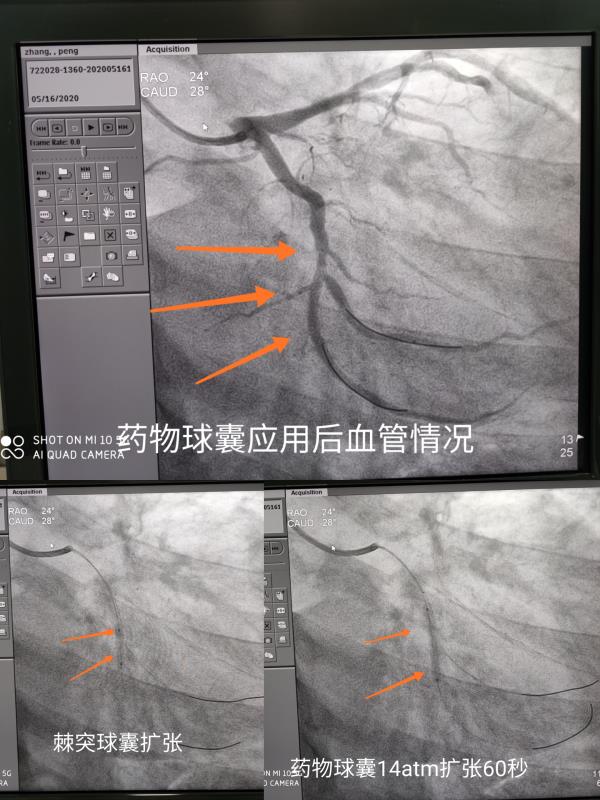

2020年5月7日,市人民医院急诊科接诊了一例突发胸痛患者,心电图显示急性下壁ST段抬高型心肌梗死,询问其病史,患者虽然只有40多岁,但此次已经是第五次心肌梗死发病。时间就是生命,急诊胸痛团队立即启动胸痛绿色通道,行急诊冠脉介入治疗。患者冠脉造影提示回旋支中段闭塞,血栓负荷较重,行PTCA及冠脉血栓抽吸术,血流恢复并发现闭塞处为分叉病变。在与患者家属进行病情交流后,考虑患者多方面因素,后予以行经皮冠状动脉药物球囊扩张成形术,手术十分顺利,术后在医护人员的精心照料下,患者现已康复出院。

“在治疗分叉病变、支架内再狭窄、小血管病变、弥漫性病变等药物支架疗效不佳或无法治疗等病变时,心脏药物球囊通过局部向冠状动脉血管壁释放抗增殖药物,抑制血管内膜增生,减少内膜炎症反应,与传统心脏支架植入术相比,可降低心脏支架使用的临床风险,术后患者服用抗凝药物的时间减少。”急诊科武双全副主任介绍说。药物球囊扩张术既能达到血管成形,又没有支架植入。药物球囊介入术为介入医师提供了新的治疗策略,使患者多了一个选择。